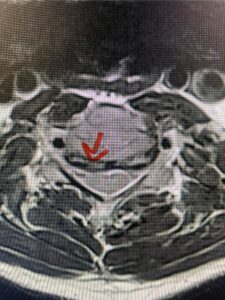

In this next case, this patient is a 47 year-old female who presents with intractable low back pain with severe pain, numbness, and weakness in the right lower extremity that had gotten progressively worse over a year. The patient had failed conservative management including physical therapy and epidurals. She was noted to have ⅘ weakness of plantar flexion. MRI demonstrated a large right L5-S1 disc herniation with severe compression of the descending right S1 nerve root (Fig 3). It was decided to perform a right L5-S1 hemilaminectomy for removal of the disc fragment and decompress the S1 nerve root. When you expose the disc, one must be certain to release any anterior adhesions to the nerve root in order to prevent a dural tear during retraction of the nerve root. It is also important to make sure during exposure and you finally encounter the dura after removing the ligamentum and fat, to make sure you are looking at the nerve root and not the main trunk of the thecal sac because if you don’t you can avulse or damage the nerve root if you retract the wrong structure.

Fig. 3a: Sagittal and axial T2-weighted lumbar MRI images demonstrating large right L5-S1 disc herniation (red arrows)

Fig. 3b

We found a massive subligamentous herniation which had to be revealed by having your partner retract the freed nerve root with a nerve root retractor and putting slight downward pressure on the more medial and anterior disc space. There is nothing more satisfying when the jelly (disc fragment) of the annulus (donut) comes squirting out and you remove a large chunk of disc material that clearly was stretching the ligament membrane and compressing the nerve root. This does cause back pain in addition to radiculopathy not only by the component of mechanical compression but also the stretching of the nerves within the ligament. We performed this surgery and noted that the nerve root was a very angry red color or hyperemic and we removed a large subligamentous fragment. The patient had improvement of her preoperative radicular symptoms.